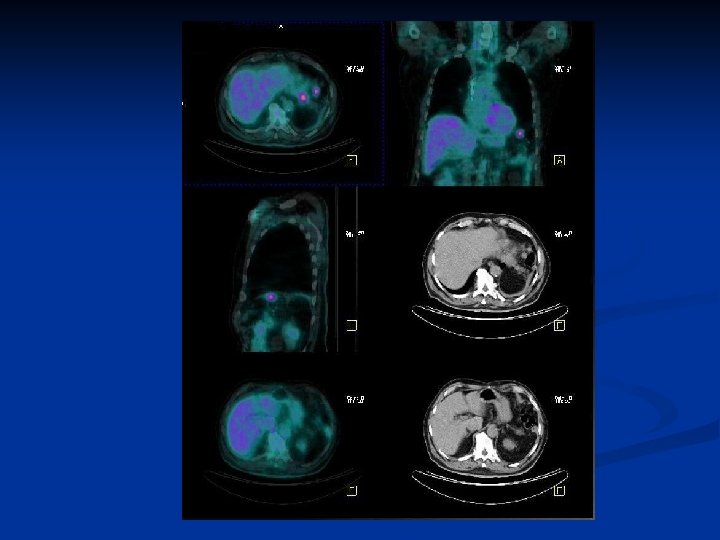

Cas n° 2 n n Homme 80 ans Cancer colique Réascention des ACE en cours de surveillance Bilan radio standard: négatif